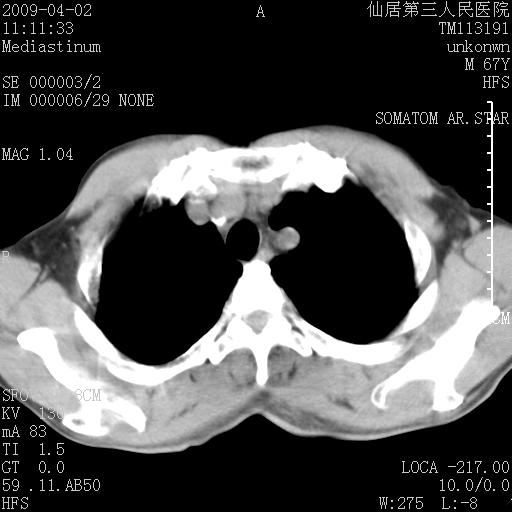

患者老年男性,乏力畏寒来诊,摄胸片示右下肺感染性病变,抗炎两周后复查胸片,无好转有进展。

后做ct平扫表现如下:

病灶呈蜂窝征,纵隔多个淋巴结肿大;肺泡癌需考虑

考虑双肺间质性改变(间质纤维化?)伴右肺下叶感染。